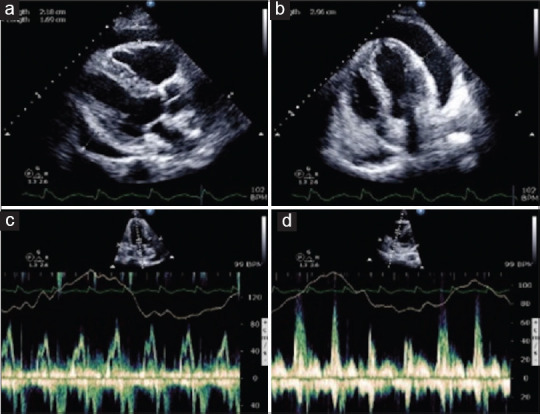

Acute pericarditis and cardiac tamponade after COVID-19 vaccination.

接种 Covid-19 疫苗后出现急性心包炎和心脏填塞。